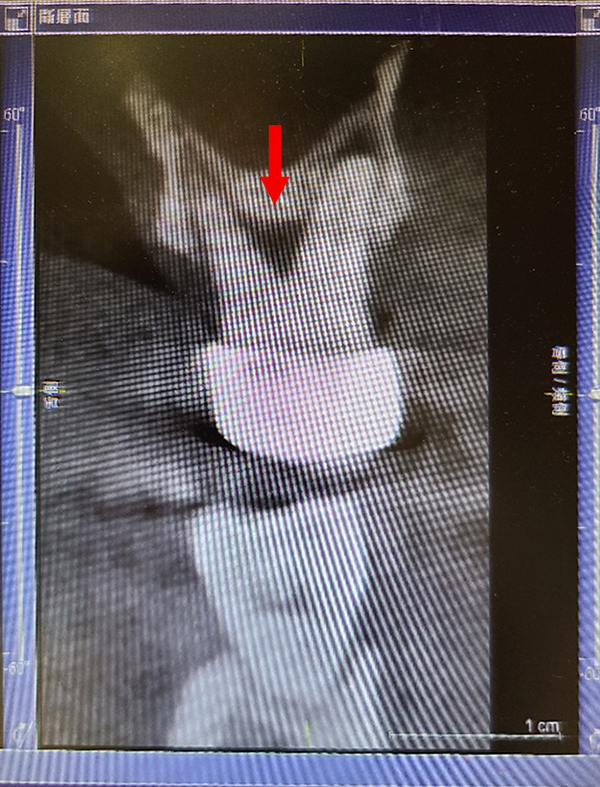

顯微鏡下進行牙周病治療,使用高倍數醫療顯微鏡,360度檢查每顆牙齒牙周狀況,紅色箭頭處可見造成牙周病主因的牙齦下牙結石,使用特殊顯微超音波工具清除後,可見乾淨的牙根表面,幾無出血(黃色箭頭處)。